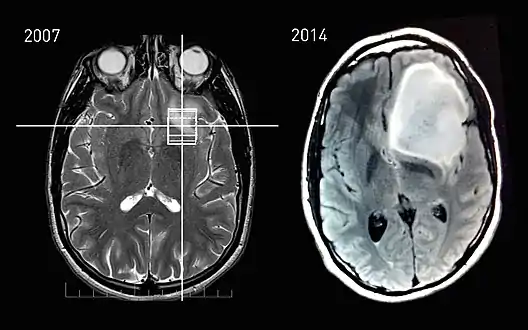

An X-ray computed tomography (CT) or magnetic resonance imaging (MRI) scan is necessary to characterize the extent of these tumors (size, location, consistency). CT will usually show distortion of third and lateral ventricles with displacement of anterior and middle cerebral arteries. Histologic analysis is necessary for grading diagnosis.

In the first stage of diagnosis the doctor will take a history of symptoms and perform a basic neurological exam, including an eye exam and tests of vision, balance, coordination, and mental status. The doctor will then require a CT scan and MRI of the patient's brain. During a CT scan, X-rays of the patient's brain are taken from many different directions. These are then combined by a computer, producing a cross-sectional image of the brain. For an MRI, the patient relaxes in a tunnel-like instrument while the brain is subjected to changes of magnetic field. An image is produced based on the behavior of the brain's water molecules in response to the magnetic fields. A special dye may be injected into a vein before these scans to provide contrast and make tumors easier to identify.